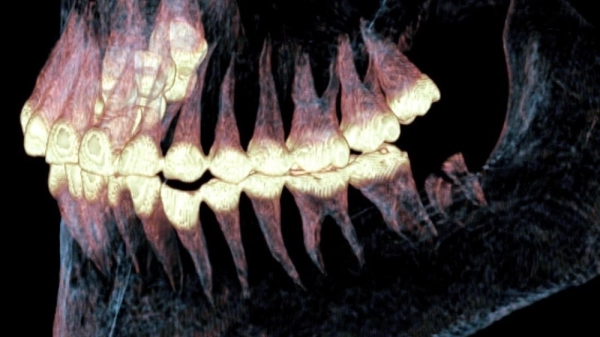

Компьютерную томографию провели в Лаборатории ядерной и инновационной медицины физического факультета Новосибирского государственного университета. Томограф позволил виртуально «удалить» эти покровы и создать точную цифровую, а затем и физическую 3D-модель черепа.

После того как была создана 3D-модель черепа, за её изучение взялся доктор медицинских наук, рентгенолог Андрей Летягин. Он обнаружил нечто невероятное — следы сложной хирургической операции с протезированием разрушенного сустава. Специалист увидел два тонких искусственных канала диаметром 1,53 миллиметра, просверленных в кости нижней челюсти. Внутри каналов сохранились остатки эластичного материала — предположительно, конского волоса или сухожилия животного. Это была примитивная конструкция, которая удерживала суставные поверхности вместе и позволяла женщине двигать челюстью. То есть сустав работал!

«Скорее всего, во время операции пациентка держала рот раскрытым, — рассуждает Андрей Летягин. — Просверливали эти каналы, вероятно, в два этапа — в горизонтальном и вертикальном направлениях. На КТ-изображениях было явно видно, что кость просверлена очень ровно, а вокруг отверстий наросла костная ткань. Выявленное кольцевое уплотнение костной ткани указывает на прижизненное происхождение этих каналов».